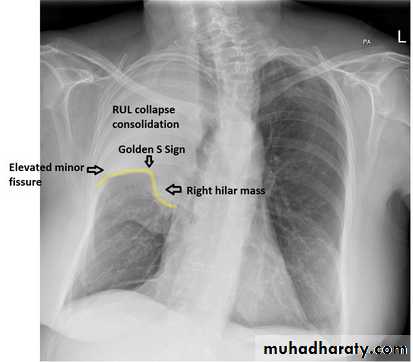

Nodular (coin) lesion in the left upper lung with irregular edge (most probably cancinoma